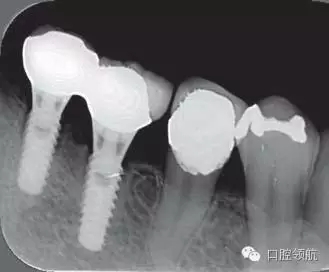

2005年4月時,可見(左下第6顆牙) 部的種植體達(dá)到第4螺紋,(左下第7顆牙)的種植體周圍觀察到位于第3螺紋的頸部進(jìn)行性骨吸收(圖4)。到2009年9月時,骨吸收像的周圍有了明顯的骨密度增加影像(圖5)。

圖5 骨吸收像的周圍有了明顯的骨密度增高影像(2009年9月)